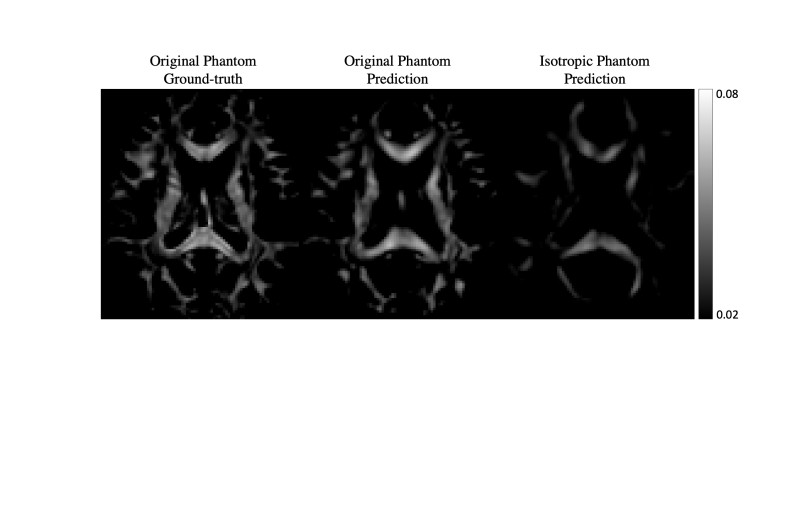

To better understand the contribution of the learned prior to the reconstructed MSA of DeepSTI, we tested DeepSTI on simulated phase generated from a fully isotropic STI brain phantom (manually set MSA=0 across the whole brain). Furthermore, to mimic the more realistic case of partially isotropic regions caused by lesions, we also tested our method on a local isotropic phantom where two cubic isotropic regions of size (10voxel)3superscript10voxel3(10~{}\text{voxel})^{3} were inserted in the original anisotropic phantom (Fig. 10).

Fig. 9(a) shows the histogram of MSA values predicted by DeepSTI in major fiber regions (defined by voxels with ground-truth MSA >>0.02 ppm) for the original anisotropic phantom and the fully isotropic phantom, while Fig. 9(b) shows corresponding MSA maps. Although DeepSTI naturally does not predict exactly zero MSA for the isotropic phantom, it is clear that the MSA values predicted by DeepSTI are significantly smaller in the isotropic phantom than in the original phantom. Fig. 10 depicts the MSA maps predicted by DeepSTI for the local isotropic phantom, where a notable decrease in anisotropy can be observed in DeepSTI’s prediction for both of the manually-defined isotropic local regions (indicated by red arrows).

Refer to caption

(a)

(b)

Figure 9: DeepSTI predicted MSA for a fully isotropic phantom. (a) Histogram of MSA values in major fiber regions defined by voxels with ground-truth anisotropy >0.02ppmabsent0.02𝑝𝑝𝑚>0.02ppm. (b) DeepSTI predicted MSA for the original anisotropic phantom and the isotropic phantom.

Fig. 9 presents the results on an unrealistic but interesting case, where reconstruction of a completely isotropic brain phantom is attempted. Although the results indeed show decreased MSA in white matter areas compared to the anisotropic phantom, the predicted anisotropy values are not completely zero. This is expected, because the solution given by DeepSTI can be broadly regarded as a maximum a posteriori (MAP) estimate for the ill-posed STI reconstruction problem, maximizing the probability of the solution under the learned prior from data. A completely isotropic brain has probability zero in the distribution of human STI (and, by extension, in all the training data used to train the model) and thus a completely isotropic reconstruction should never be expected. Yet, this does not mean that regions of abnormal anisotropy, or areas that are mostly isotropic in white matter, could not be approximately reconstructed. On the contrary, this is demonstrated by the experiment with the locally-isotropic regions in Fig. 10, as well as by the results on the MS patients.